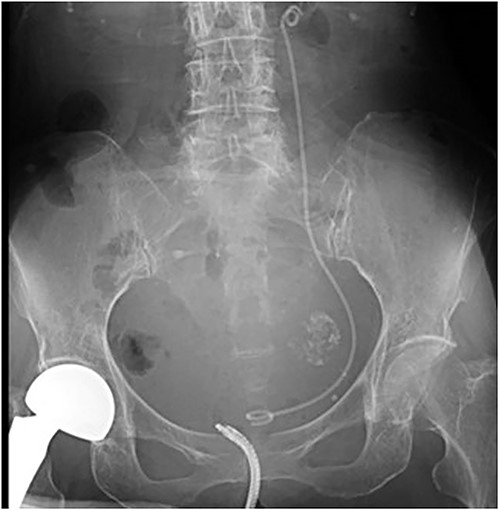

A 78-year-old woman (height, 161 cm; weight, 35 kg) had undergone total gastrectomy for gastric cancer; pathological examinations had revealed signet ring cell carcinoma with invasion into the serosa. One year and 4 months after the surgery, she presented to our hospital with fever, anorexia and weight gain. Computed tomography (CT) revealed left ureteral stricture and hydronephrosis caused by recurrent peritoneal dissemination (Fig. 1). Blood tests revealed decreased renal function and an increase in the inflammatory response. Based on these findings, a diagnosis of left obstructive acute pyelonephritis was made, prompting a decision to place a ureteral stent to relieve the obstruction. Using a flexible cystoscope fluoroscopically, a 6 Fr, 24 cm double-J ureteral stent was inserted into the left ureter. The guidewire passed smoothly, and good coiling was achieved both proximally and distally with no apparent complications (Fig. 2). Two weeks after stent placement, the patient recovered with improvements in left hydronephrosis and renal function.

A post-operative plain abdominal X-ray; the ureteral stent is properly placed as seen in a plain abdominal X-ray.